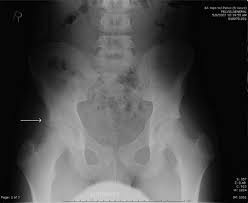

Apophyseal Avulsion Fracture Ric Size from i1.wp.com They are serious injuries that most often occur in people aged 65 and older. People who fracture their hip sometimes need surgery to fix the fracture or replace the hip. These injuries can be extremely painful, and may take months to heal. An avulsion fracture is a fracture in which part of the bone breaks off from the rest of the bone. Sometimes you can get an avulsion fracture in other bones, such as the hand. They are more common in children avulsion fractures are caused by trauma. What causes a hip fracture? Ebraheim's educational animated video describes the condition of avulsion fractures around the hip in adolescence.

Timely, accurate diagnosis is imperative so proper treatment can be initiated. Ebraheim's educational animated video describes the condition of avulsion fractures around the hip in adolescence. Call 999 and ask for an ambulance. I was doing high jump and twisted my body and in the process my muscle ripped my growth bone off. Hip fractures are classified according to their anatomical location as intracapsular, which involves the femoral head and neck, and extracapsular, which includes intertrochanteric, trochanteric, an. With an avulsion fracture, an injury to the bone occurs near where the bone attaches to a tendon or ligament. Symptoms of ankle avulsion fracture are similar to ankle sprain. Call your health care provider if your pain doesn't go away, or if you notice swelling. Preparing for an avulsion fracture in the ankle? Avulsion fractures of the hip and. Avulsion fracture of the iliac crest is an uncommon pathology. This happens when a muscle or tendon connected to the hip bone suddenly tightens so hard that it pulls off part of the bone. I am 15 and did it to my hip/ upper pelvic bone.

With an avulsion fracture, an injury to the bone occurs near where the bone attaches to a tendon or ligament. Anyone can suffer an avulsion fracture of the ankle, but athletes and children are more prone to them than the rest of us. This happens when a muscle or tendon connected to the hip bone suddenly tightens so hard that it pulls off part of the bone. Ebraheim's educational animated video describes the condition of avulsion fractures around the hip in adolescence. An avulsion fracture occurs when a small chunk of bone attached to a tendon or the hip, elbow and ankle are the most common locations for avulsion fractures in the young athlete. If you think you've fractured your hip, you'll need to go to hospital as soon as possible. In acute avulsion fractures, there is usually a clear preceding traumatic incident. When to seek medical help. The causes of hip fracture are very different in young and elderly patients. With age, the bones can become weak and brittle. Other causes include cancer and injury. They usually happen when a bone is moving one way, and a tendon or ligament is suddenly pulled the opposite way. Hip apophyseal injuries in young athletes are a fairly rare problem, and often go unrecognized by health professionals.

Acute Avulsion Of The Iliac Crest Apophysis In An Adolescent Indoor Soccer from www.jbsr.be I am 15 and did it to my hip/ upper pelvic bone. An avulsion fracture is a fracture in which part of the bone breaks off from the rest of the bone. When the fracture happens, the tendon or these fractures most often affect bones in the elbow, hip, and ankle. What causes a hip fracture? There are numerous sites at which these occur. Hip pain in children is always a potentially serious and needs urgent assessment. Teenagers are more likely to have this injury than younger children. Hip fractures can limit mobility and independence.

Pain in the hip area may be referred from the knee joint or from structures in the inguinal canal, testis (including torsion) and lower abdomen, or from the lower back. Teenagers are more likely to have this injury than younger children. The causes of hip fracture are very different in young and elderly patients. Other causes include cancer and injury. Hip fracture occurs in approximately 341,000 persons in the united states each year. Read about causes, treatment options, available mobility devices, tips for recovery, and more. This happens when a muscle or tendon connected to the hip bone suddenly tightens so hard that it pulls off part of the bone. In acute avulsion fractures, there is usually a clear preceding traumatic incident. A hip fracture is a break in the bones of your hip. A hip fracture is a common injury, especially in people with osteoporosis. I was doing high jump and twisted my body and in the process my muscle ripped my growth bone off. A broken hip in older people is often partly the result of weakening bones from osteoporosis. This most commonly occurs at the ischial tuberosity where the hamstrings attach, or the iliac pain at the bony part on the front of the hip may be an anterior superior iliac spine avulsion fracture.